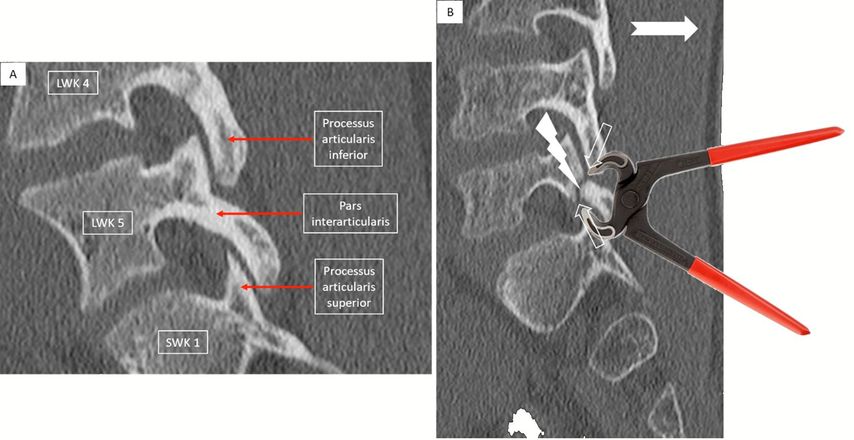

Die Prävalenz der Spondylolyse liegt bei ungefähr 6%, wobei relevante ethnische Unterschiede bestehen.1 Dies und die Tatsache, dass bei 15–70% von erstgradig Verwandten von Betroffenen ebenfalls eine Spondylolyse vorliegt, legt eine hereditäre Prädisposition für einen Pars-Defekt nahe.2,3 Knaben sind doppelt so häufig betroffen.4 Die fehlende Inzidenz der isthmischen Spondylolyse bei Neugeborenen und nicht gehfähigen Menschen und die nachgewiesenermassen erhöhte Inzidenz bei jugendlichen Leistungssportlern unterstreicht den Stellenwert der mechanischen Faktoren bei der Entstehung des Pars-Defektes.1,3,5 Mit der Evolution des aufrechten Ganges und der damit verbundenen Lordosierung der Lendenwirbelsäule (LWS) mit am stärksten ausgeprägter Lordose im Bereich der unteren LWS und des lumbosakralen Übergangs und unter Berücksichtigung der lokalen Anatomie und der Ausrichtung der Facettengelenke ist nachvollziehbar, dass die isthmische Spondylolyse in 85–95% der Fälle den 5. Lendenwirbel betrifft.6 Bei repetitiver Extension und/oder Rotation der LWS kann der Processus articularis inferior des kranial gelegenen Wirbels und der Processus articularis superior des kaudal gelegenen Wirbels im Sinne eines Nussknacker- oder Kneifzangenmechanismus auf die Pars interarticularis des betroffenen Wirbels drücken (Abb. 1). Capener hat diese mechanische Pathogenese bereits 1931 beschrieben und sie hat weiterhin Gültigkeit.7

Abb. 1: Bild A zeigt einen sagittalen Schnitt einer Computertomografie (CT) der unteren Lendenwirbelsäule (LWS) mit intakter Pars interarticularis des 5. Lendenwirbels (LWK 5). Ebenfalls gekennzeichnet sind der Processus articularis inferior vom 4. Lendenwirbel (LWK 4) sowie der Processus articularis superior des 1. Sakralwirbels (SWK 1). Abbildung B illustriert den Pathomechanismus bei der Entstehung der isthmischen Spondylolyse (Defekt im Bereich der Pars interarticularis): Durch repetitive Reklination oder Rotation (ausgefüllter Pfeil) können der Processus articularis inferior des kranial gelegenen Wirbels und der Processus articularis superior des kaudalen Wirbels wie eine Kneifzange oder ein Nussknacker auf die Pars interarticularis drücken und zu einem Ermüdungsbruch (Blitz-Pfeil) führen